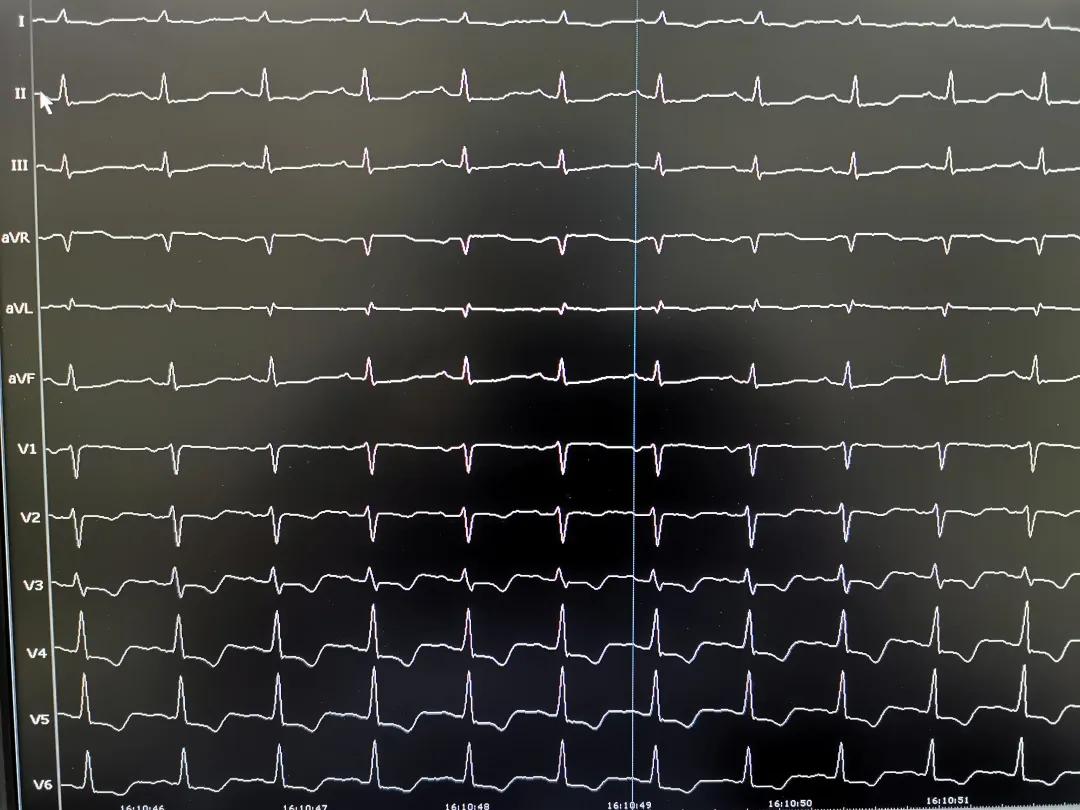

术前心电图

经查体,华先生的频发室性早搏多年,动态心电显示早搏近 5 万次/日,根据图形判断早搏极可能为乳头肌起源——是一种罕见室性早搏,治疗难度最大。仔细评估后,北部宽仁医院心内科主任耿召华教授向华先生建议,采用最新的心腔内超声指导下射频消融术进行治疗。

经过周密的准备,12 月 11 日,耿召华教授带领心内科团队,使用目前最先进的三维超声导管(Cartosound)进行左心室的构建,精准标测出前组、后组乳头肌的位置,寻找最好靶点。最终在前组乳头肌根部找到室性早搏的起源点,消融数秒后,早搏消失。

为进一步验证病灶是否真的已被阻断,有没有恢复的可能。术中,耿教授继续分次消融 2 分多钟,持续观察半小时,并静脉滴注异丙肾上腺素激发,仍然再无早搏,射频消融成功,手术台上的华先生瞬间即感受到了久违的胸腔内的舒适感。